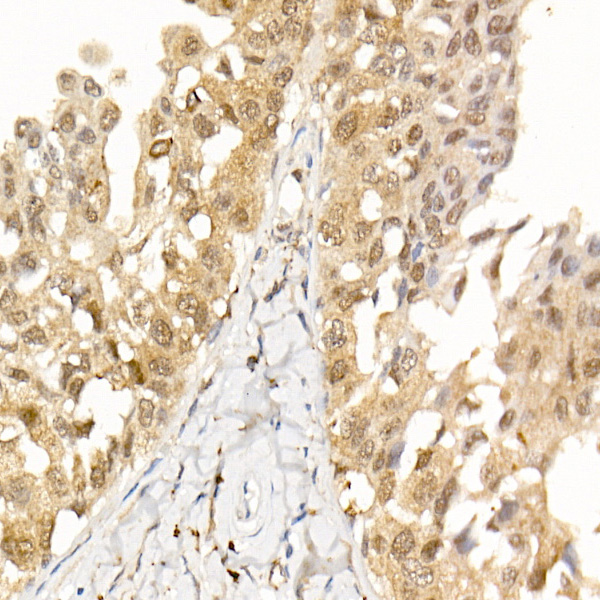

| Immunohistochemistry analysis of paraffin-embedded Human breast cancer using [KO Validated] AKT1 Rabbit mAb (A22770) at dilution of 1:100 (40x lens). High pressure antigen retrieval performed with 0.01M Citrate Bufferr (pH 6.0) prior to IHC staining. |